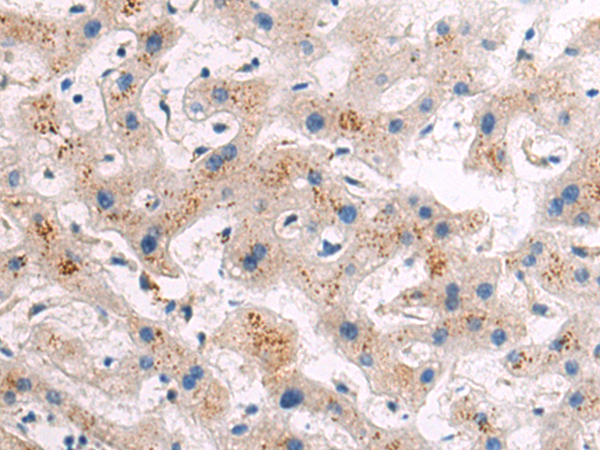

分类: 科研抗体货号: P06881别名: CP24; HCAI; CYP24; HCINF1; P450-CC24应用: WB,IHC反应种属: Human, Rat